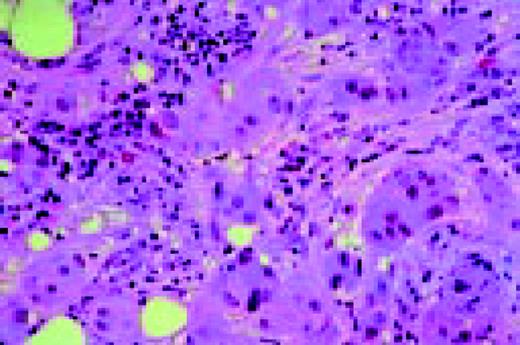

Slide L53

Hodgkin's disease associated with AIDS, bone marrow biopsy, H&E. Total replacement of normal bone marrow by an abnormal infiltrate including two Reed-Sternberg cells (top right).FIG53